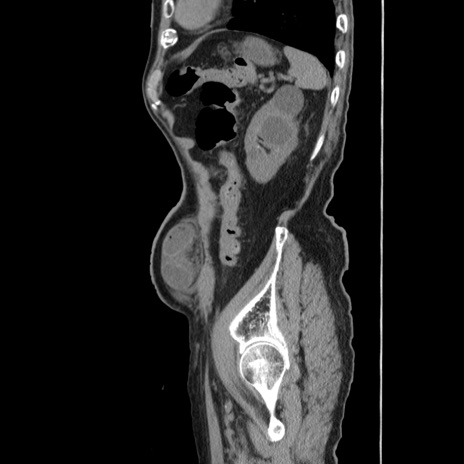

症例24(矢状断像)

【症例】80歳代男性

【主訴】左側腹部痛、嘔吐

【現病歴】本日早朝より左腹部に痛みあり。昼頃嘔吐認めたため、救急要請。

【既往歴】直腸癌(Mile手術)、胆摘

【身体所見】意識清明、BT 35.9℃、BP 221/93mmHg、SpO2 97%(RA) 、腹部:左ストーマ周囲に限局性の腹部膨隆あり。 膨隆部自発痛・圧痛あり・軟。

【データ】WBC 7700、CRP 0.09